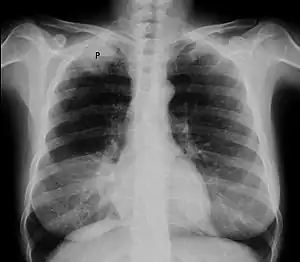

![]() | |

| Chest radiograph showing a Pancoast tumor (labeled as P, non-small cell lung carcinoma, right lung), from a 47-year-old female smoker. | |